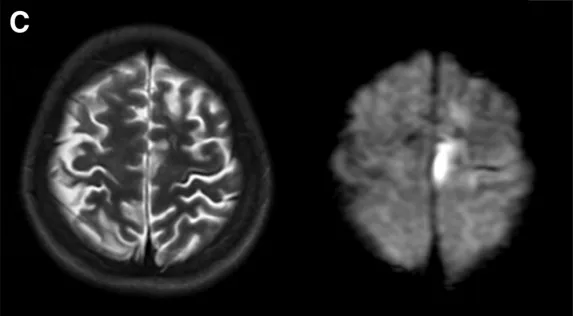

入院时术前影像学检查结果:T2加权磁共振成像(左图)及弥散加权成像(右图)显示左侧额叶存在新发脑梗死病灶。

然而出乎所有人意料,仅一个月后,小林的病情突然急转直下:她再次出现构音障碍,右侧肢体也开始无力,复查发现左侧额叶出现新的脑梗死病灶。更为危急的是,她还并发了甲状腺危象,表现为高热、心动过速、高血压等症状。此时小林的fT4、fT3指标再次急剧升高,脑部缺血状况亦持续加重。